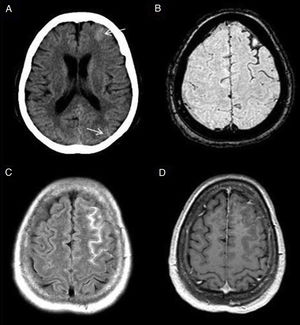

Subarachnoid haemorrhage (SAH). The CT image shows a faint hyperdensity in the left superior frontal and left parieto-occipital sulci (arrows) in relation to non-traumatic SAH (A). The haematic content of the superior frontal and prerolandic sulci produces a susceptibility hypointensity in the T2*FFE sequence (B) and a hyperintensity in the FLAIR sequence (C). No enhancement on T1 sequence with IVC (D). No aneurysms or vascular anomalies were found on digital subtraction angiography.

CSF pulsatility artifact. Axial FLAIR images show non-pathological CSF signal hyperintensity in the peribulbar (A), prepontine (B) and suprasellar (C) cisterns. Magnetic susceptibility artifact. The CT image (D) shows a millimetre-sized foreign body of metallic density in the subcutaneous cellular tissue (arrow) causing a magnetic susceptibility artefact on T2* gradient-echo sequences (E) and a linear signal hyperintensity artefact on FLAIR (F) in the underlying subarachnoid space (arrow).

Oxygen therapy artifact. Patient who was receiving supplemental oxygen. The FLAIR sequence (A) shows a very faint and diffuse increase in CSF intensity in the frontoparietal convexity sulci that disappeared in the control MRI after withdrawal of oxygen therapy (B). Artefact due to vascular pulsatility. Pulsatility artefact in the cistern of the bulbocerebellar angle on the left side (C), produced by the throbbing of the basilar artery, simulating a lesion. This image is not identified in the T1-weighted sequence with IVC (D).